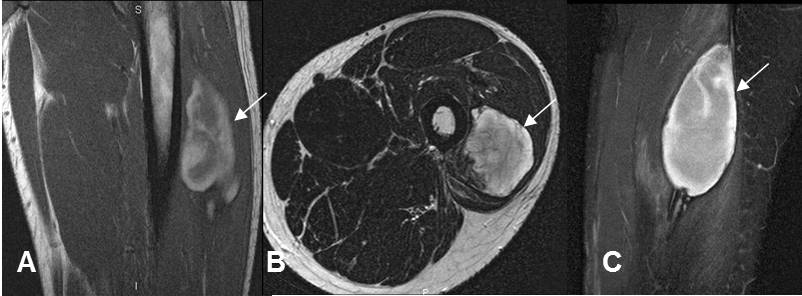

Fig 151. Hematoma muscular subagudo.

A: RM coronal en T1. Colección heterogénea, con áreas hiperintensas por evolución subaguda, en el músculo vasto externo.

B: RM axial en T2 y C: RM sagital en STIR. Colección intramuscular, definida e hiperintensa.